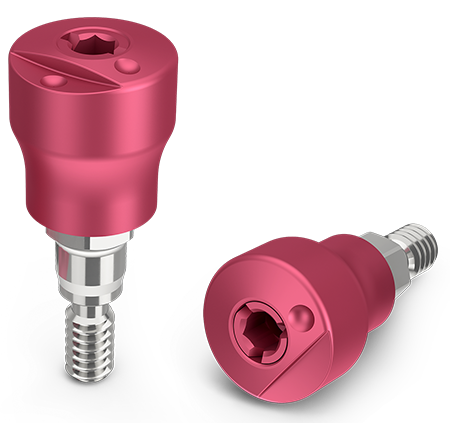

Encode Emergence Features

Heal Naturally. Impress Easily.

Easy, efficient and proven Encode technology with contemporary emergence profile designs, intuitive codes and pink matte appearance.

Eliminate the healing abutment and impression coping or scan body swapping process, while delivering soft tissue healing with natural emergence profile.

Available in various emergence profile diameters and heights (2.9, 3, 5, and 7-mm).